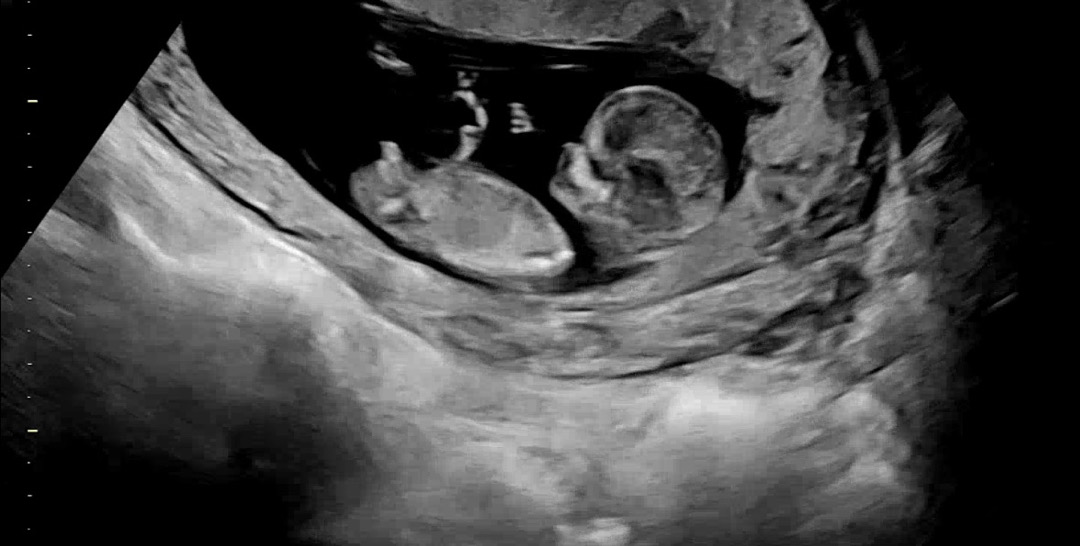

12주 0일차 각도법 문의드려요

막상 성별예측해보려하니 뭔가 두근대네요,,ㅎ 혹시 아들일까요, 딸일까요,,?? 오늘 12주 0일차 초음파입니다 !

아들같긴한데 다리인지 소중이인지 헷갈리네용,,